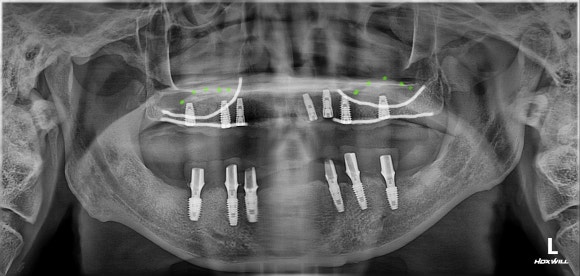

​원래 환자분의 뼈가 흰색 실선처럼 얇았던 상태라 임플란트를 튼튼하게 쓰려면 녹색 점선처럼 뼈를 만들어 줘야 했습니다.

상악동 거상술이라는 테크닉을 이용했습니다.

​또한 상악동 거상술을 이용해 만든 뼈도 단단하게 자기 뼈가 되고 있는 모습을 볼 수 있습니다.